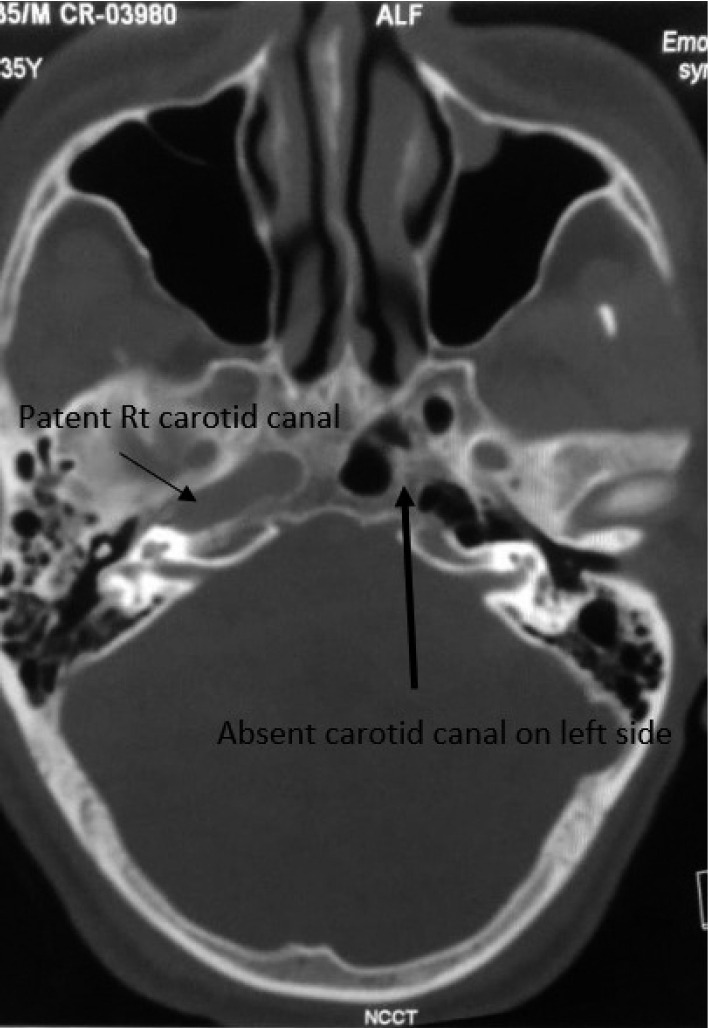

Developmental anomalies of internal carotid artery (ICA), being rare entities, are mostly asymptomatic by themselves because of good collateral supply. However, when present with other associated intracranial anomalies requiring treatment, there can be catastrophic consequences, if special attention is not paid to this condition. We present a case of 36 years old male, who reported to our emergency department with complaints of headache and loss of consciousness. He was diagnosed as a case of ruptured anterior communicating aneurysm with subarachnoid hemorrhage and agenesis of left ICA with trans-cavernous anastomosis. He underwent clipping of aneurysm and was discharged uneventfully. This report highlights the importance of skillful microsurgical clipping in extremely high-risk conditions, in contemporary era of hybrid neurosurgeons.